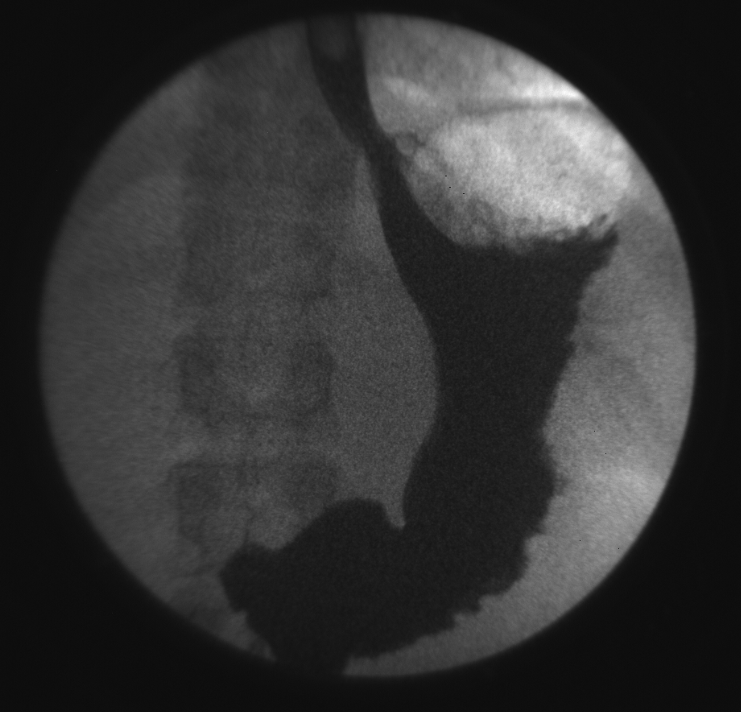

Как обещал, снимки. Снято при 75kV 1ma. Первые 2 - сделанные последовательно снимки одного объекта. Третий - сделанный чуть позже. Может, они что-то прояснят?

001.bmp (1.61 Mb) · 002.bmp (1.51 Mb) · 101.bmp (1.49 Mb)

судя по картинкам всеж больше проблемы в работе ССЯ или проблема в настройках ССD камеры, на помехи непохоже...